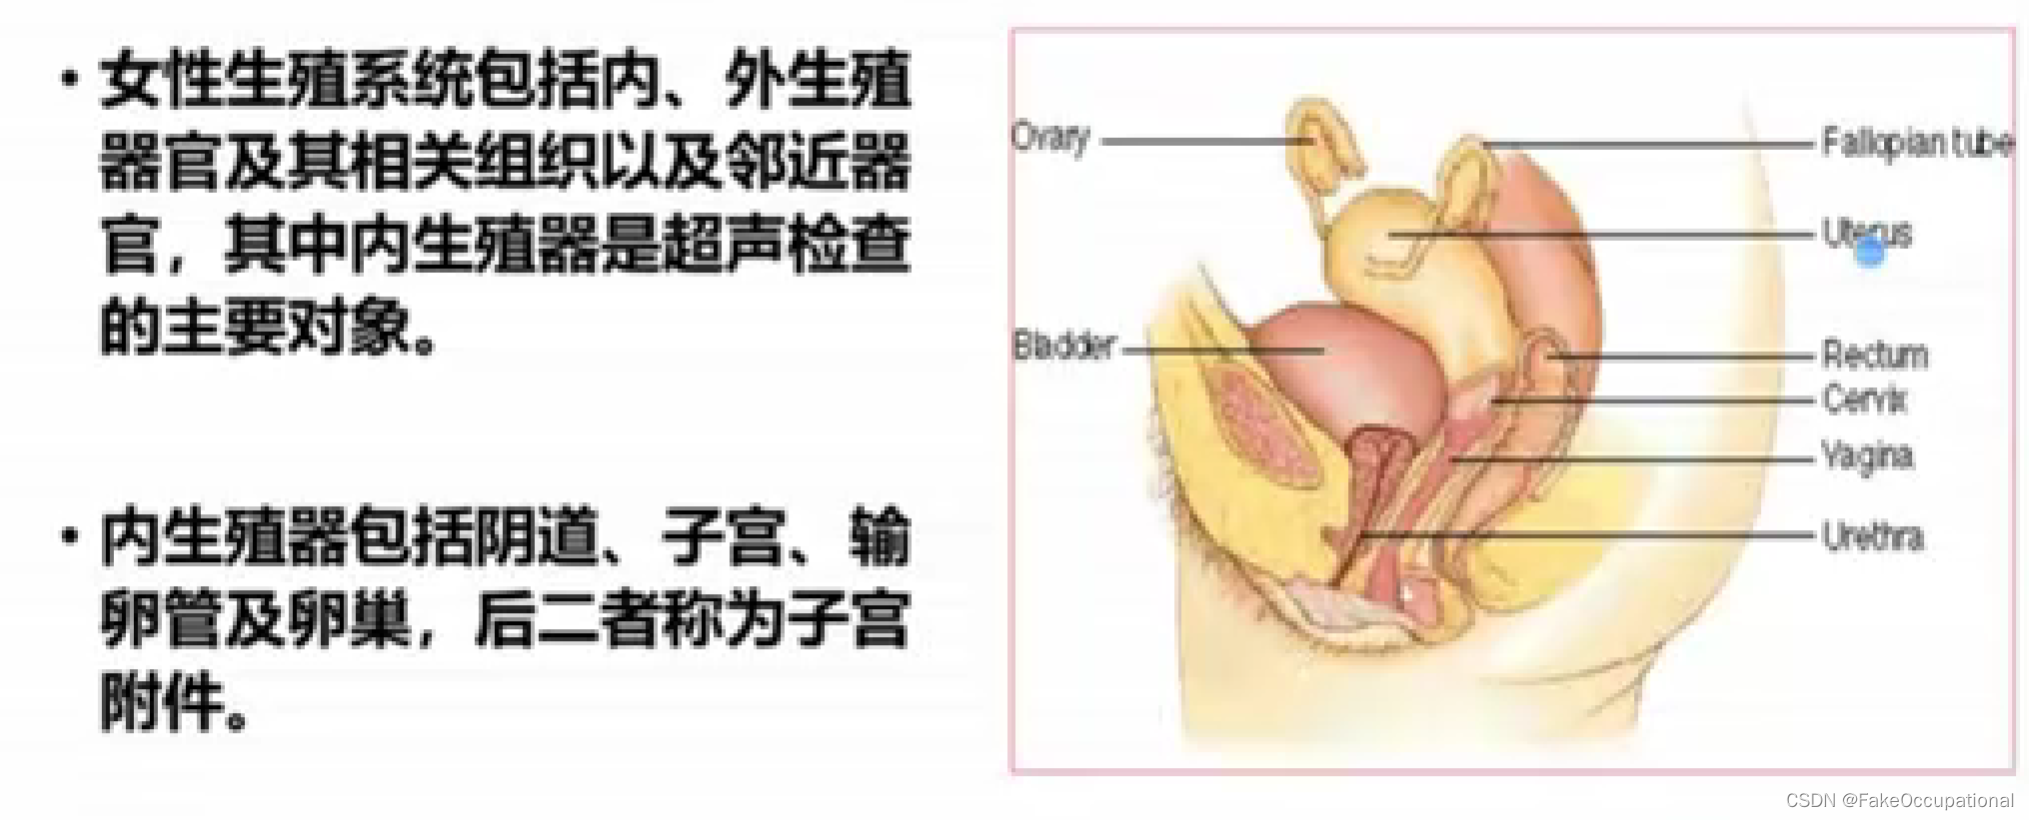

妇科超声(已和谐)

正常子宫和卵巢声像图